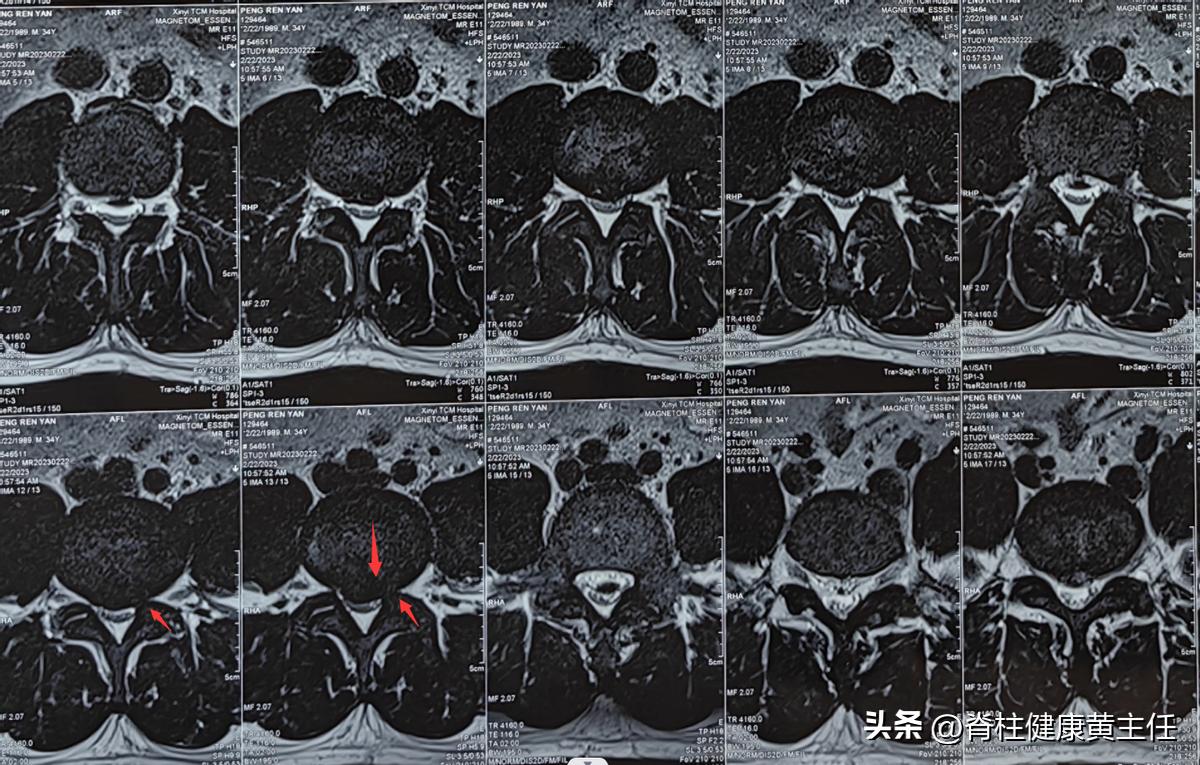

2023.2.22外院腰椎MR报告:L3/4、L4/5、L5/S1椎间盘膨出并突出,L3/4、L4/5水平椎管狭窄,L4/5、L5/S1双侧侧隐窝狭窄并神经根受压。

2023.03.18外院腰椎CT报告:L3/4、L4/5、L5/S1椎间盘向后突出,相应硬膜囊受压,L4/5、L5/S1双侧神经根受压。